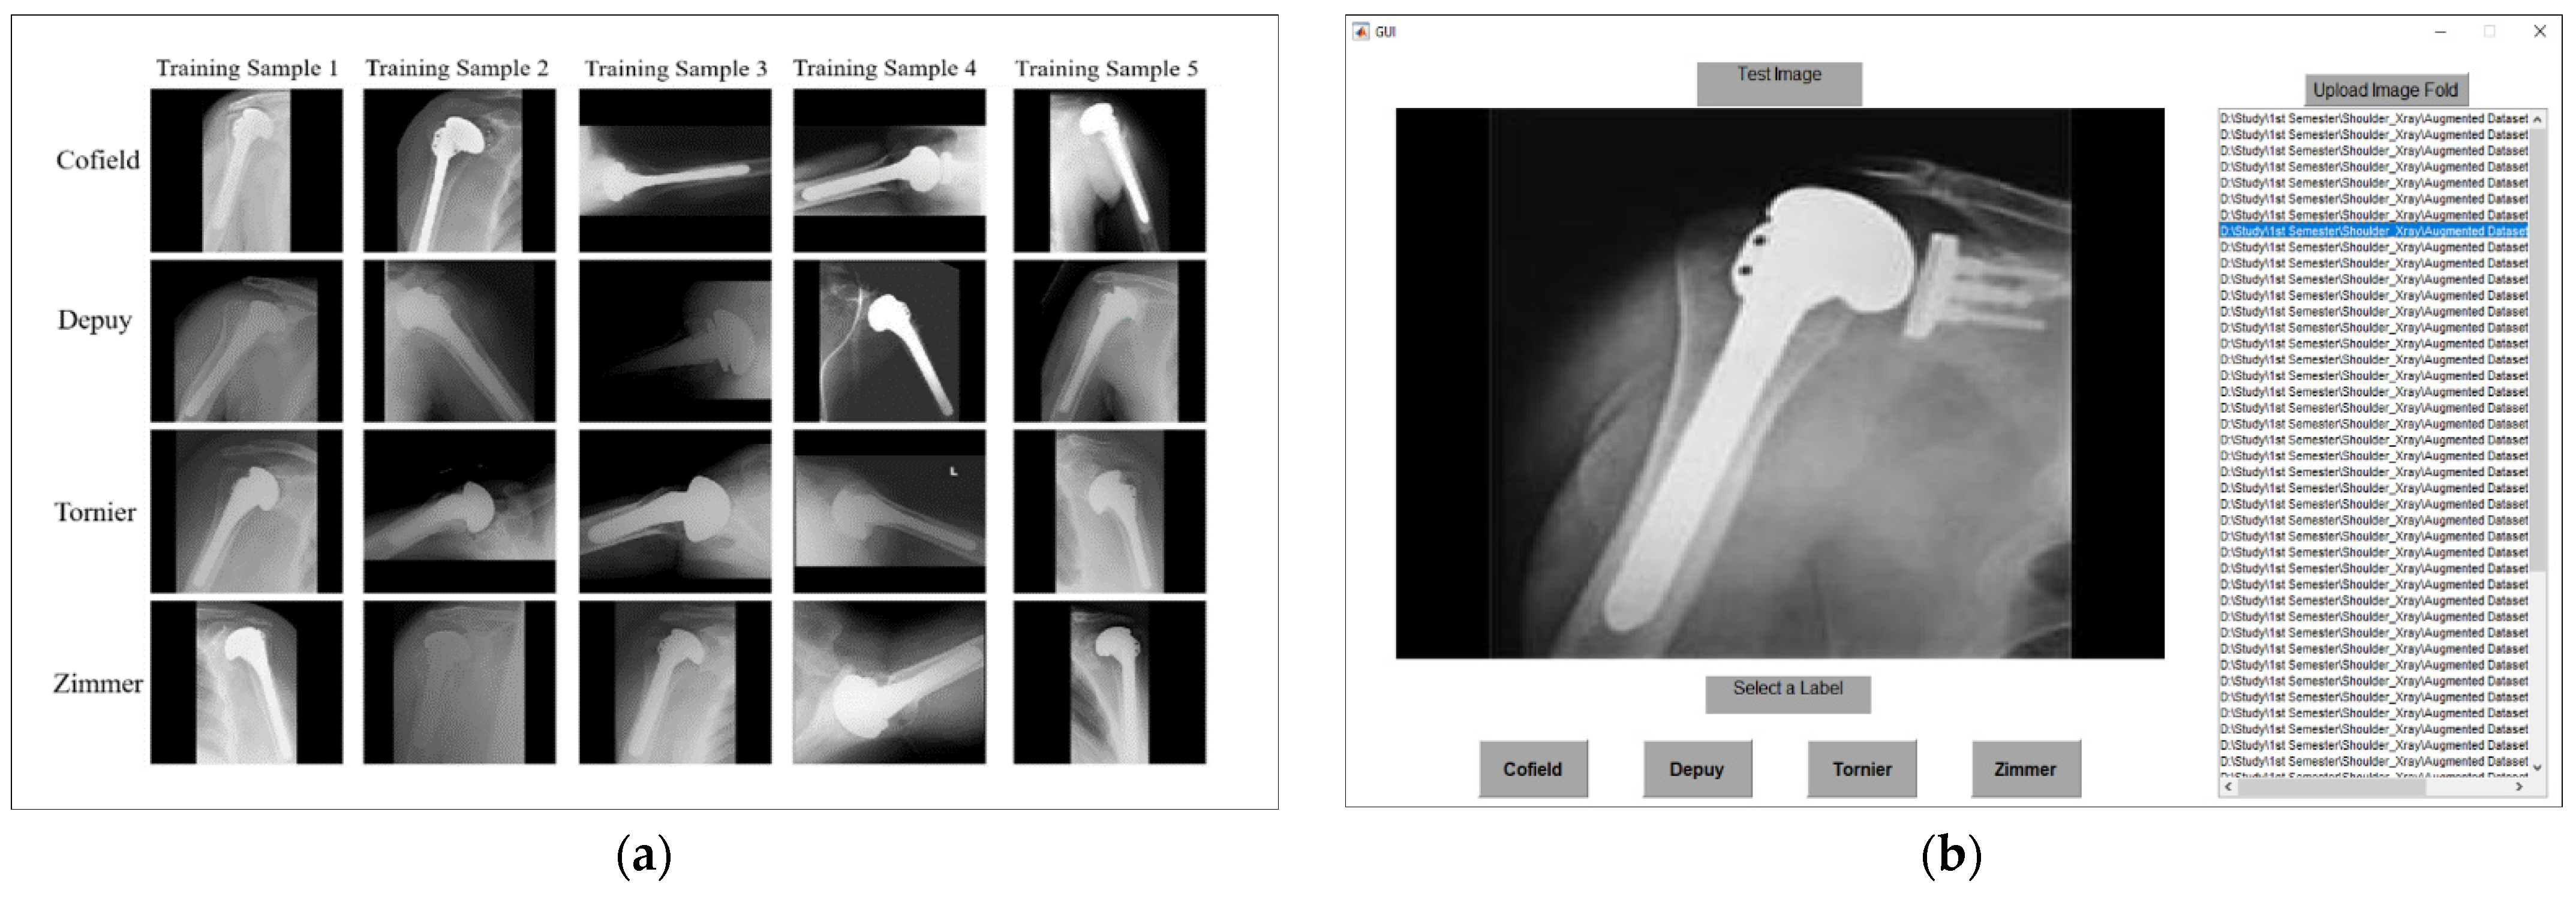

4.1. Dataset and Experimental Setups